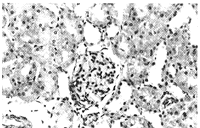

2.5 肾组织光镜下形态学改变 与1组、2组相比,3组、5组近曲小管上皮细胞普遍呈浊肿及水泡变性,可见肾小管坏死,皮质区尤为明显,胞质内胆色素颗粒沉积明显增多,管腔内可见脱落的坏死细胞;集合管内蛋白管型增多,并见细胞管型,部分肾小球凝集,肾小囊间隙增大,间质内有大量淋巴细胞浸润,而4组改变则较3、5组为轻(见图2、3、4、5、6)。

图5 4组大鼠肾组织HE染色病理照片(×40)

Figure 5 The kidney of the rat from group 4 HE×40

, 百拇医药

图6 5组大鼠肾组织HE染色病理照片(×40)

Figure 6 The kidney of the rat from group 5 HE×40